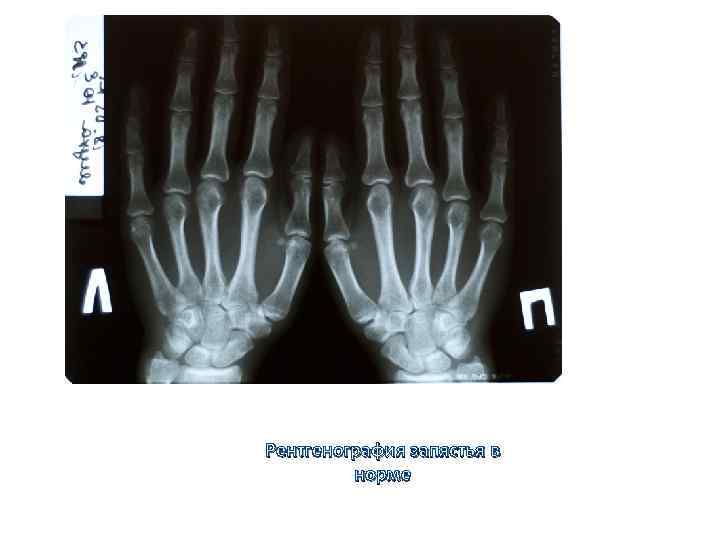

Рентгенография запястья в норме Рентгенография запястья в норме